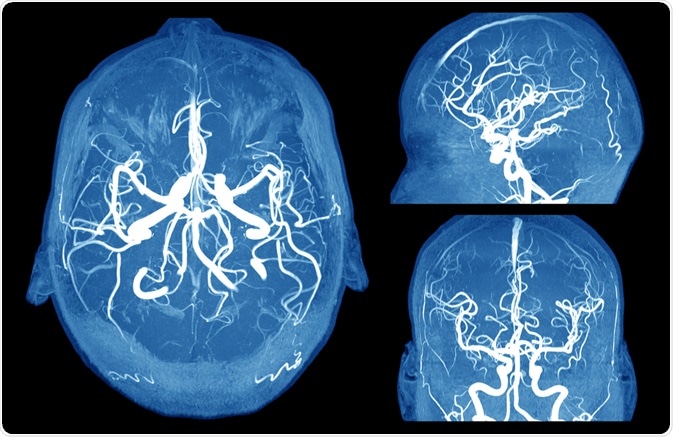

Brain Aneurysm

Image Credit: MriMan/Shutterstock.com